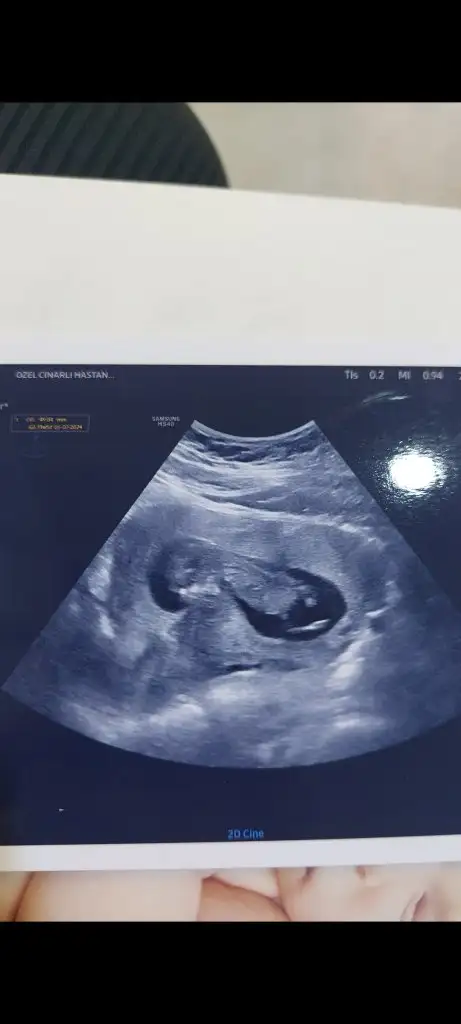

Ayyy benim minnoşum belli değil hiç ben anlayamadım bakabilir misiniz?

Eklentiler

• Screenshot_20231115_204812_com.opera.browser.webp

13,4 KB · Görüntüleme: 122